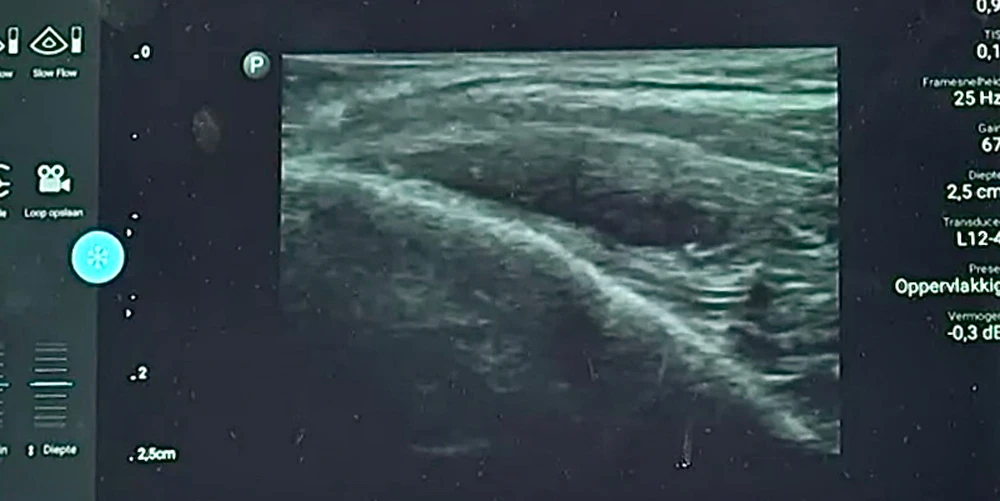

Оптимальная точка – височная. От точки пересечения лобно-височного гребня и костного края орбиты, под углом 45 градусов, латерально на 1,5 см. Прокол кожи осуществляется до надкостницы, в технике shot gun, 2–4 мм иглы должны остаться над кожей. Аспирационный тест на надкостнице – 20 секунд. При введении в этой технике, по данным УЗИ, препарат имбибирует височную мышцу и не может мигрировать (Рис. 10).

Височный лифтинг филлерами Neauvia

Рисунок 10